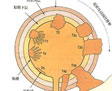

冠状动脉粥样硬化性心脏病

疾病介绍:冠状动脉粥样硬化性心脏病是冠状动脉血管发生动脉粥样硬化病变而引起血管腔狭窄或阻塞,造成心肌缺血、缺氧或坏死而导致的心脏病,常常被称为“冠心病…【详细】